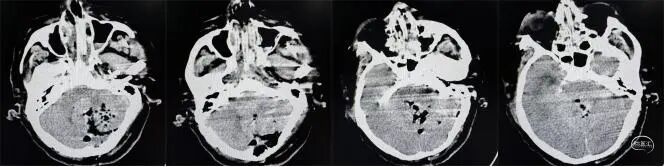

患者79岁高龄,入院前突发头痛、头晕、恶心呕吐,呕吐物为咖啡色胃内容物,伴步态不稳,紧急就诊于外院,头部CT提示“左侧小脑出血、梗阻性脑积水”。小脑出血10毫升以上即达到手术干预的关键阈值,而该患者小脑出血量高达48毫升,加之梗阻性脑积水对脑组织的压迫,患者随时面临脑疝风险,生命垂危。

患者病情危重,且既往因肾盂肾癌已行肾摘除手术,外院已不建议手术治疗,已在外院保守治疗2天,但家属治疗意愿强烈且陷入困境,他们经多方打听,通过吉大一院神经创伤外科中心付双林主任介绍,得知李晓东主任在重症颅脑疾病救治领域的深厚造诣,果断寻求帮助。李晓东主任接到求助后,立即组织团队对患者病情进行全面研判:患者不仅小脑出血量大、合并梗阻性脑积水,而且因既往肾盂肾癌单侧肾切除史,术前肾功能已出现异常(肌酐305μmol/L),手术风险与术后并发症概率大幅升高。

患者术前头部CT▲